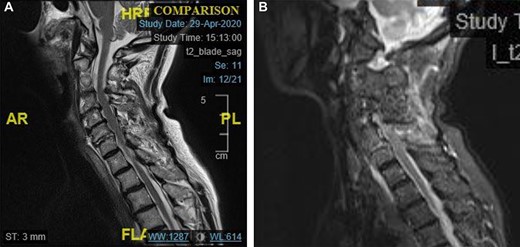

There is an acute fracture of the antero-superior osteophyte of the body of C7 (Fig. 2a). There is also opening of the cervical facet at C6/7 (Fig. 2b). There were no fractures of the vertebral bodies. It can also be appreciated that there is significant degenerative change between C4 and C7.

(a) Para-midline sagittal CT scan of the cervical spine at the time of first presentation showing a fracture of the antero-superior osteophyte of C7 (indicated with a circle). and (b) Para-midline sagittal CT scan of the cervical spine at the time of first presentation showing opening of the C6/C7 facet joint (indicated with a circle).

The MRI scan shows that the dislocation had reduced. Fig. 4a demonstrates high signal in the C6/C7 intervertebral disc.

Fig. 4b also demonstrates the injury to the posterior ligament complex at C4 to C7.

(a) Midline sagittal T2 weighted MRI image showing high signal in the C6/7 disc space. (b) Midline sagittal short-t1 inversion recovery weighted MRI image showing high signal in the posterior elements of C4–C7.